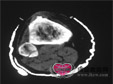

骨皮质破坏边缘模糊,因为尤文肉瘤不形成瘤骨及瘤软骨,因此破坏区及软组织内无瘤骨及钙化存在;10...